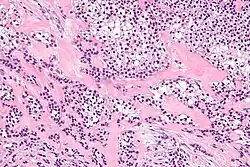

Micrograph of a hyalinizing clear cell carcinoma showing the characteristic clear cells and surrounding hyalinized stroma. H&E stain.

HCCC consist of cells with abundant clear cytoplasm, arranged in cords, trabeculae or clusters in a hyalinized stroma.[3] Nuclear pleomorphism is usually minimal and mitoses are infrequently seen.[2]

Owing to their glycogen content, which explains the "clear" appearance under the microscope, tumour cells stain with PAS. Immunostains for S100 and smooth muscle actin (SMA) are typically negative, but positive for cytokeratins and epithelial membrane antigen (EMA).